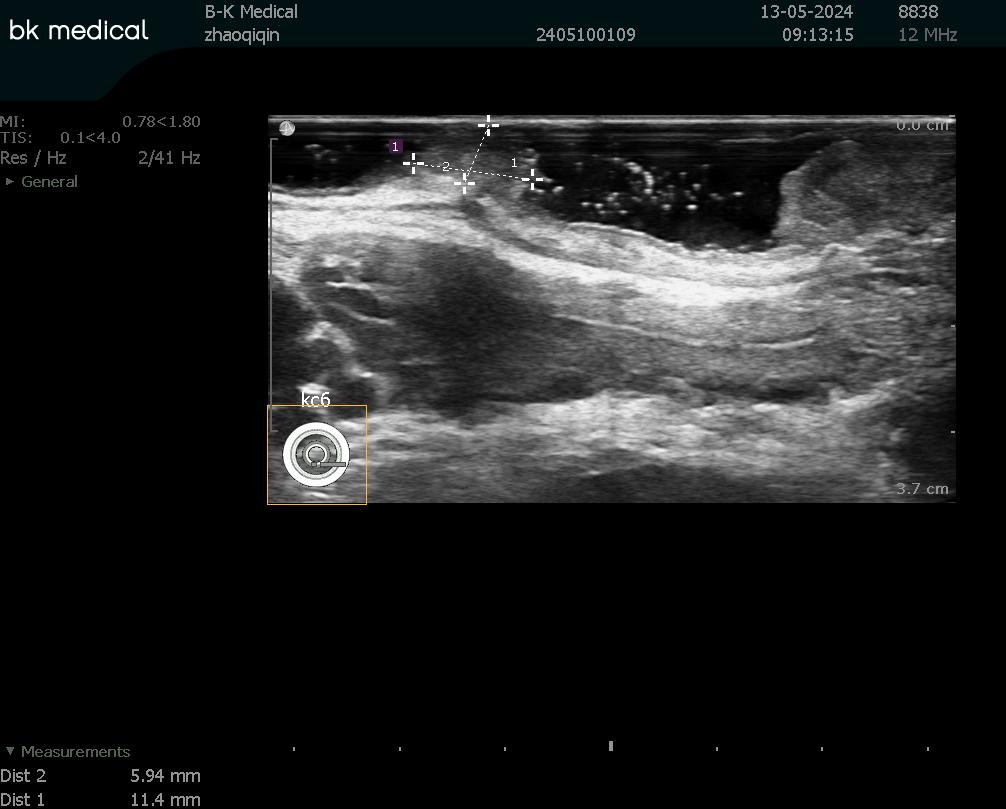

患者趙某在外院門診腸鏡檢查中發(fā)現(xiàn)直腸腫物,遂至我院就診。肛腸科楊勇副主任醫(yī)師接診后,為患者制定個性化檢查方案,完成乙狀結(jié)腸鏡及直腸腔內(nèi)超聲檢查,并完善相關(guān)輔助檢查,精準排除遠處轉(zhuǎn)移可能,全面評估肛門括約肌功能,為手術(shù)方案的制定提供了科學依據(jù)。

直腸腔內(nèi)超聲檢查對腫物浸潤層次精準定位